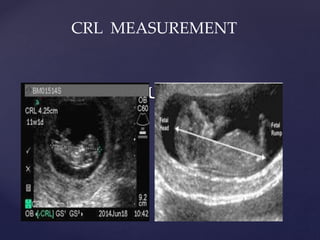

HOW TO MEASURE USING CRL

CRL MEASUREMENT

HOW TO MEASUREUSING CRL CRL MEASUREMENT